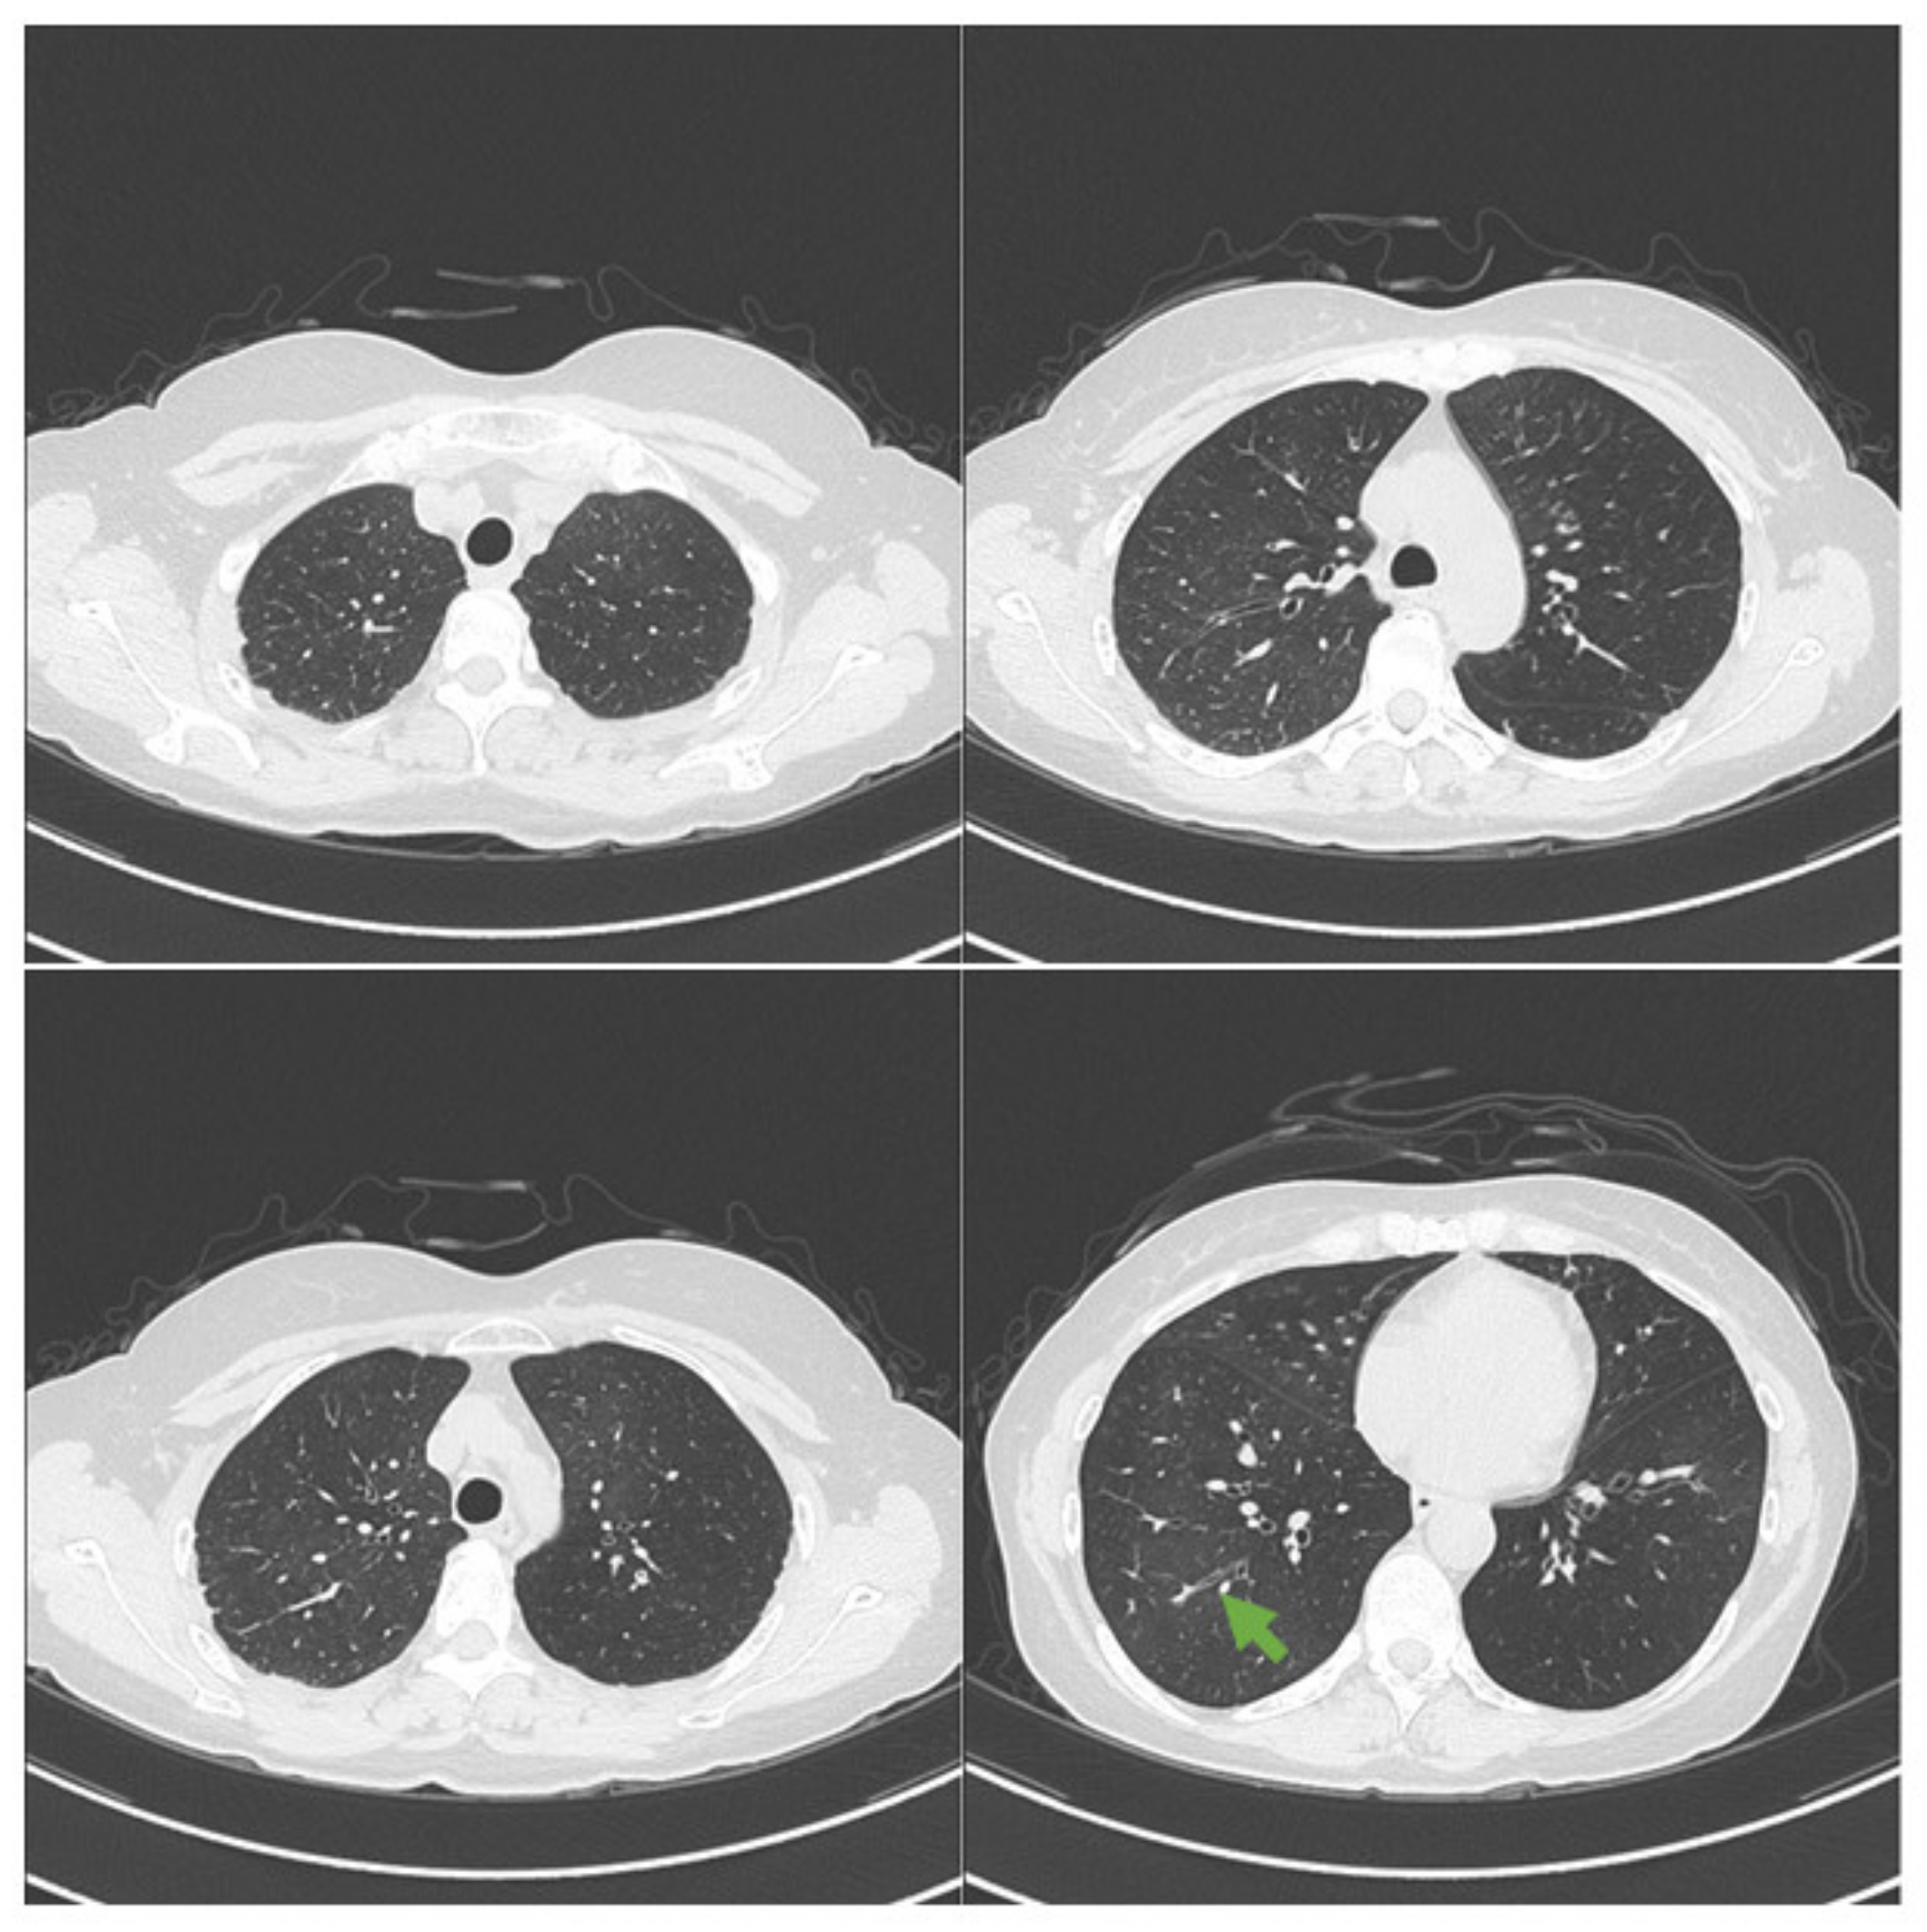

2. Case Presentation